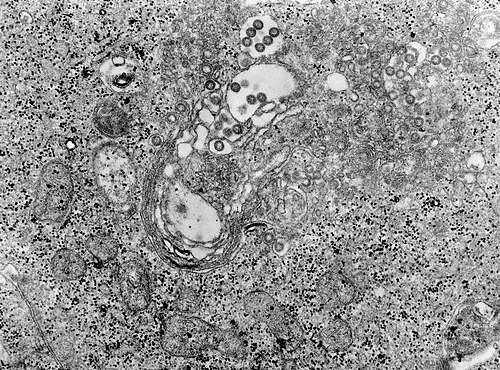

画像:リフトバレー熱ウイルスに感染した組織のTEM写真